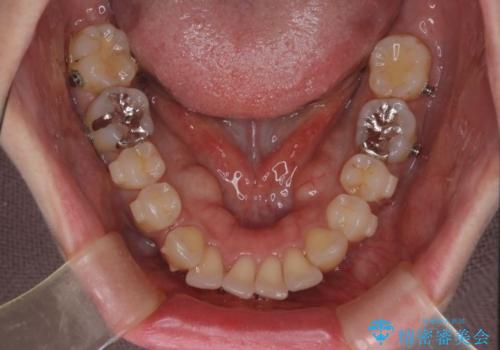

インビザラインにて抜歯矯正を行うと、高頻度で奥歯が咬み合わなくなります。

また、抜歯スペースに向けて奥歯が移動する際、必ず傾斜して移動するため、仕上がりの咬み合わせはワイヤー矯正と比べて明らかに劣ります。

抜歯スペースが閉じてからも咬みにくさ改善のためマウスピース矯正を継続するため、治療期間は長期化します。